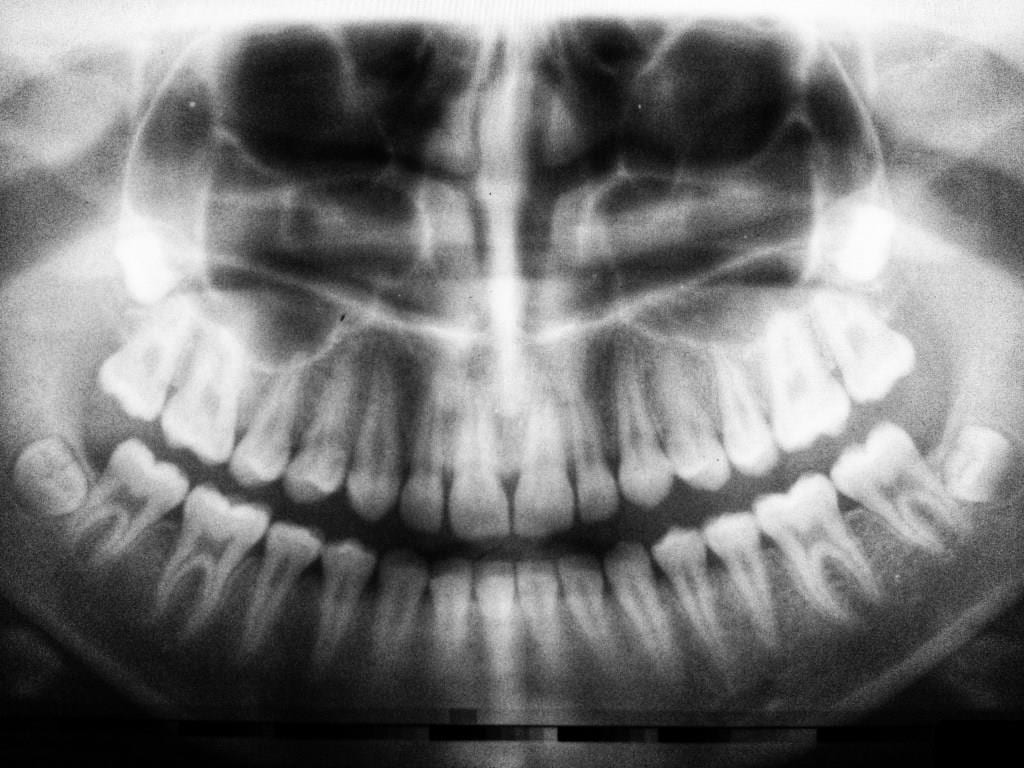

El bruxismo es un trastorno que afecta a una gran parte de la población, y sus consecuencias pueden ser severas. Este hábito involuntario de apretar o rechinar los dientes puede llevar a un desgaste dental significativo, así como a problemas en la articulación temporomandibular (ATM).

- Desgaste visible en los dientes, como superficies planas o bordes desgastados.